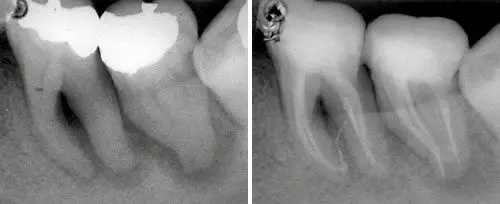

Carious Dentine Removal

Cavity Preparation